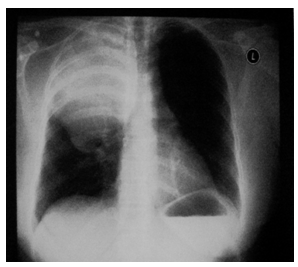

A 41year old Malay lady referred to HUSM for investigation of a mass in the right upper thorax. This mass was found incidentally on a routine chest x-ray (Figure 1 & Figure 2). Generally she is in good health. Patient only gave a history of intermittent, mild chest discomfort for duration of five years. Subject denies any history of chest trauma or chronic cough. On clinical examination, there is reduced air entry at the right upper thorax. There is no enlargement or nodule of the cervical thyroid. She has no signs or symptoms of thyroid hormone imbalance.

Figure 1 Initial AP chest X-ray, note the mass occupying the right upper thorax.